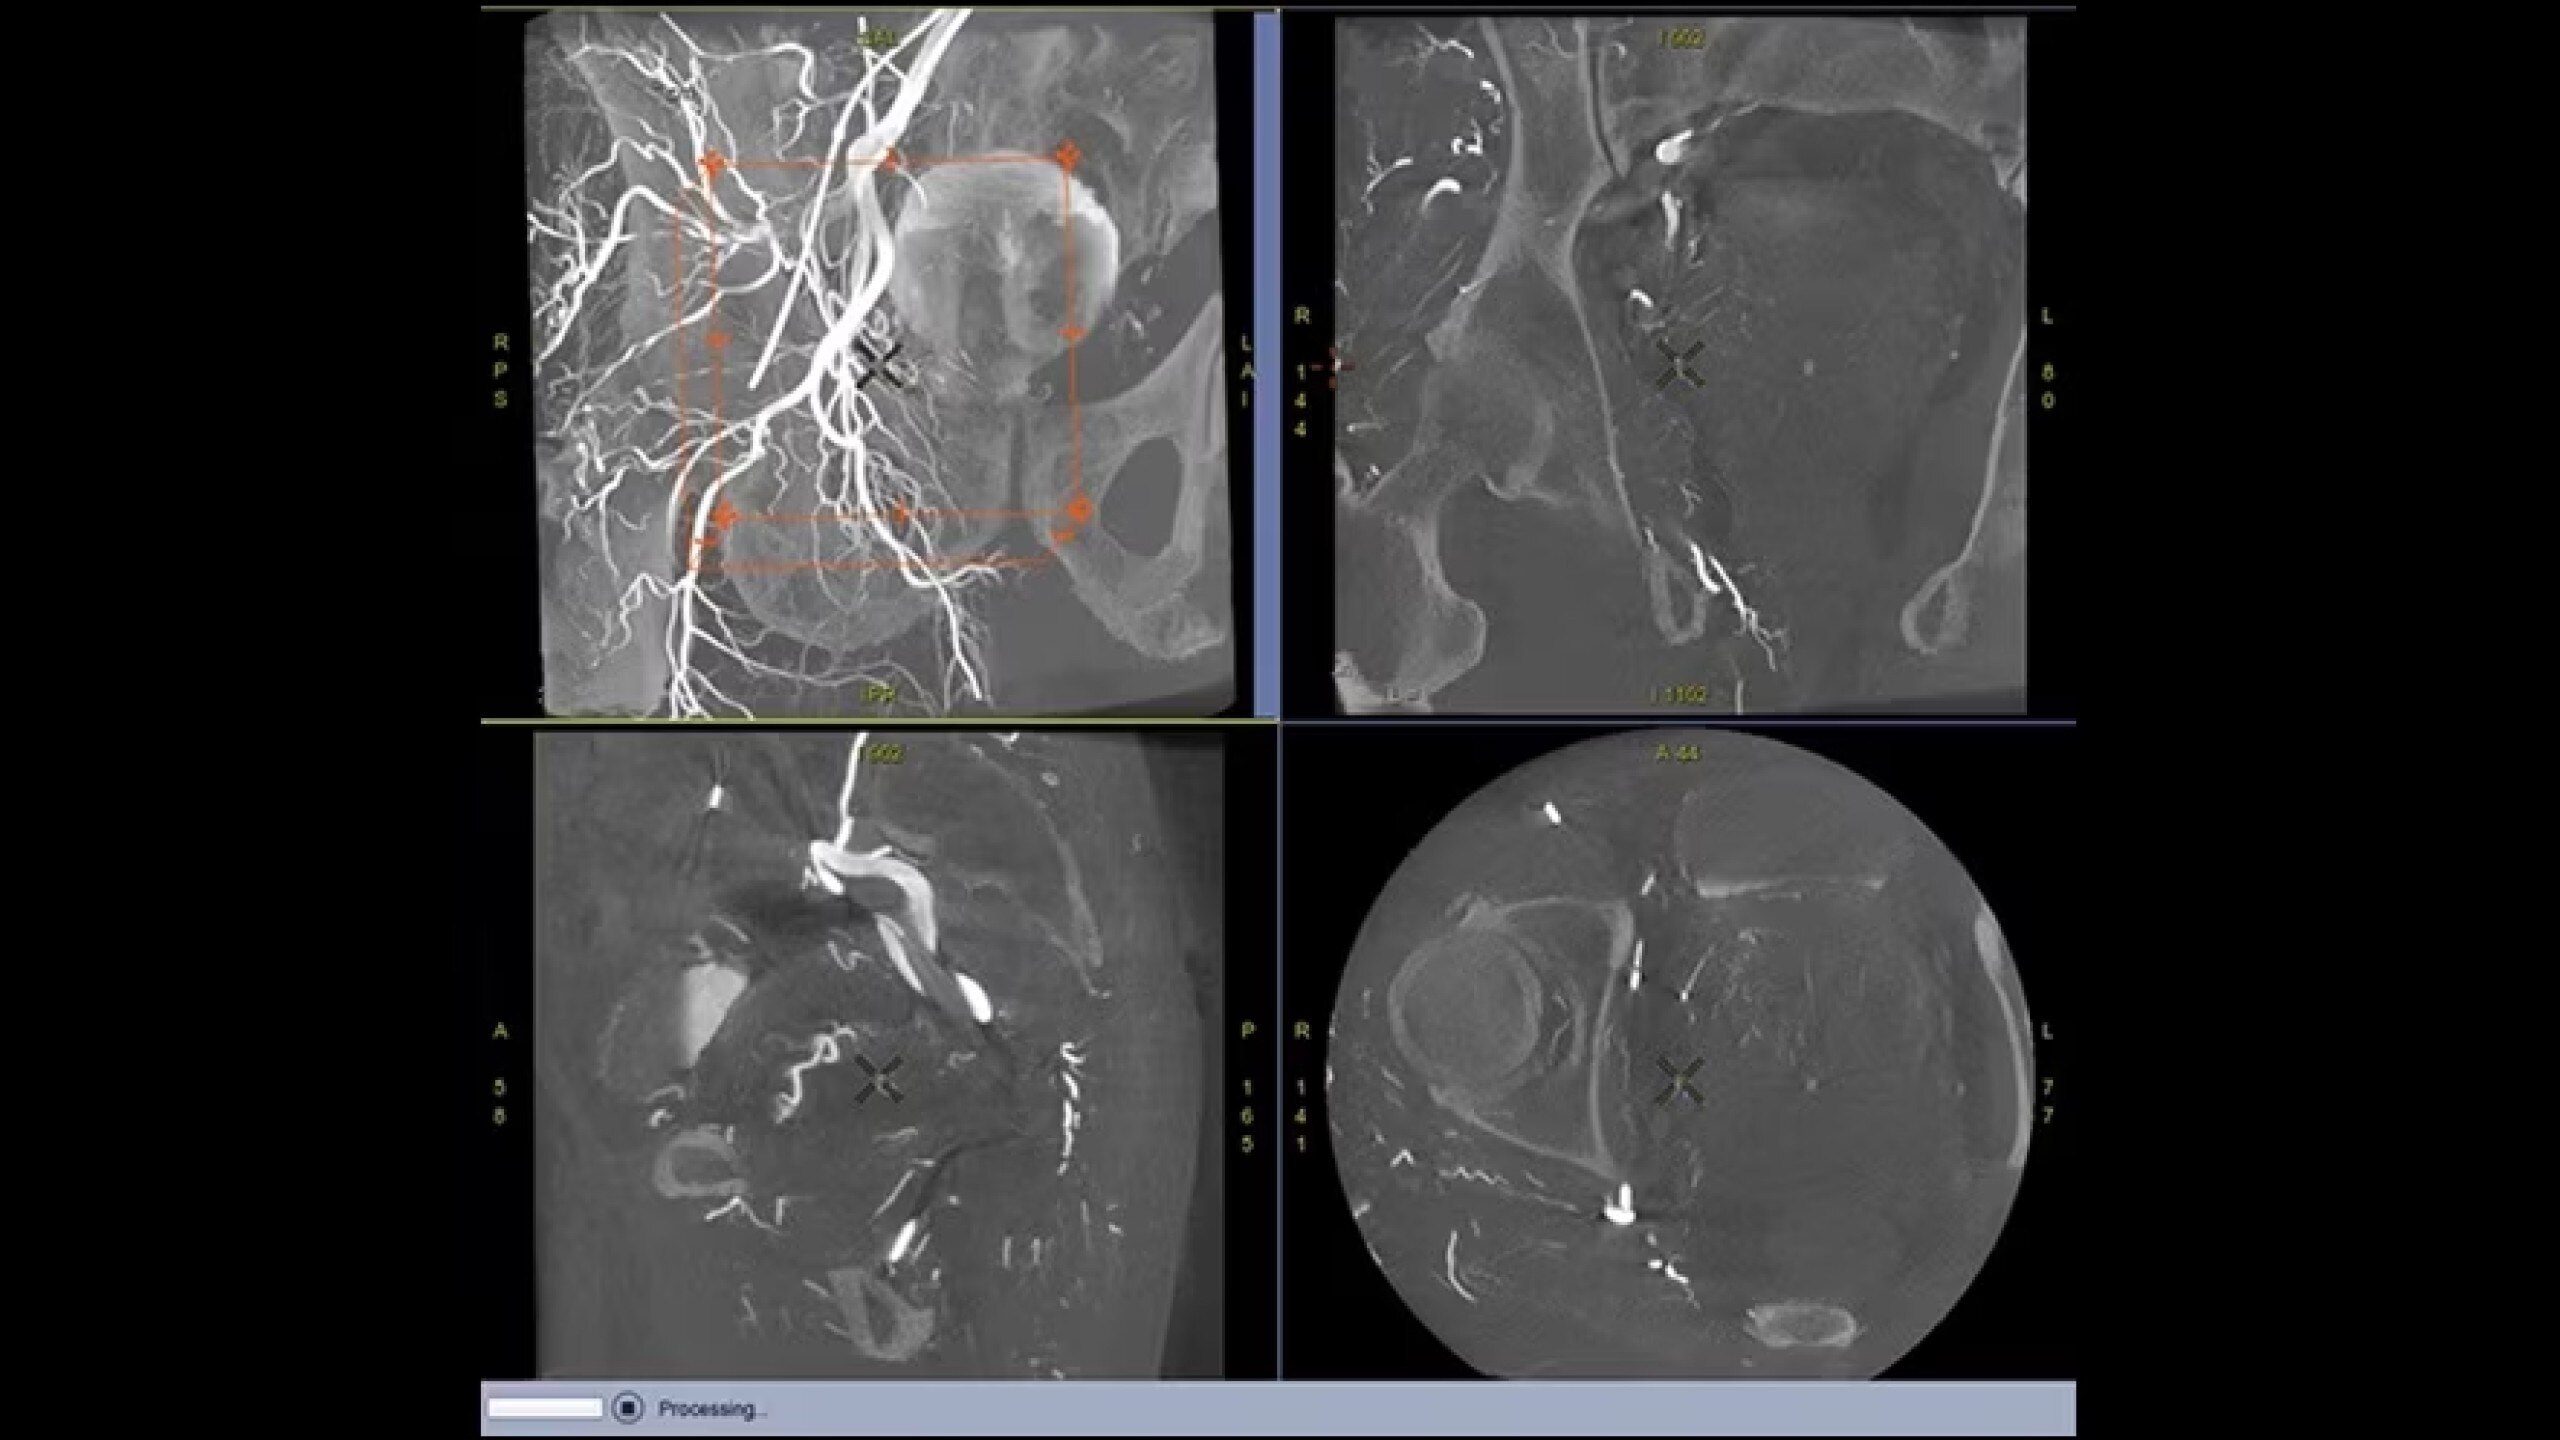

Embo ASSIST is an AI-based augmented guidance solution designed to define optimal embolization strategies and streamline your clinical workflow.

Segment vasculature from CBCT in one click

Dynamic simulation at different injection points

Visualize multiple vessels and navigate in cross sections to facilitate planning